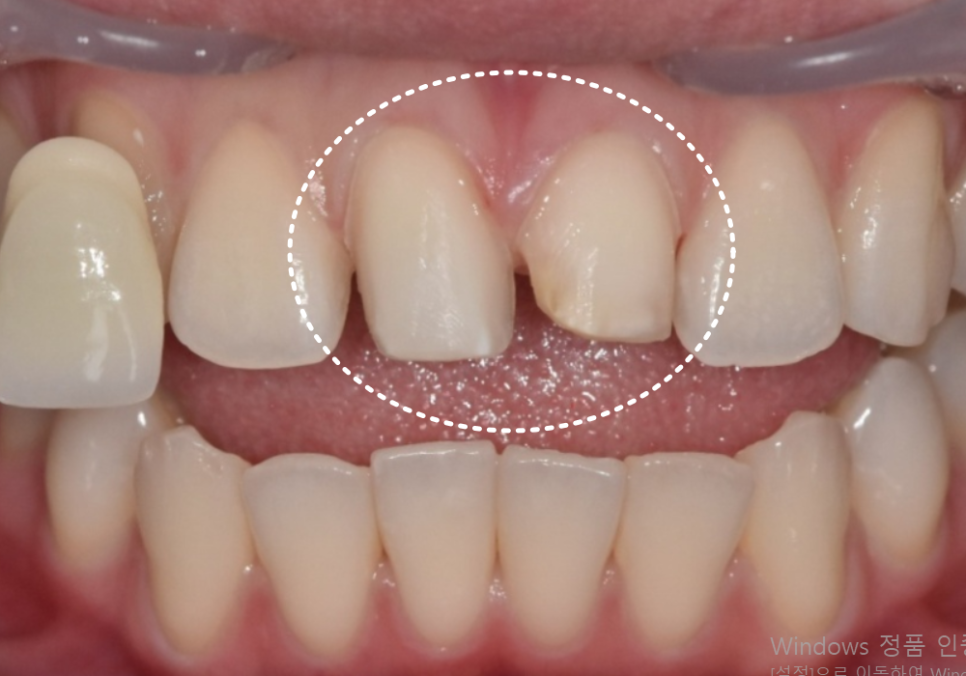

오늘 소개할 환자분도

어릴 때부터 절단교합을 갖고 계셨습니다.

한 번 앞니가 깨진 뒤 레진으로 여러 번 수복했지만

씹을 때마다 같은 자리에 힘이 실리면서

또 깨지고, 또 변색되는 상황이 반복됐습니다.

최근에는 레진이 다시 깨지면서

오른쪽과 왼쪽 앞니 길이가 다르게 보이고

앞니가 살짝 앞으로 뻗어 보이는 돌출감도 겹쳐

웃을 때마다 더 신경 쓰인다며 내원하셨습니다.

사실 이런 경우 교정 치료가

가장 정석적인 해결 방법입니다.

절단교합 자체를 개선해 앞니에 실리는

힘의 방향을 바꿔주는 것이기 때문입니다.

하지만 환자분은

교정 없이 가능한 해결책을 찾고 싶어 하셨고,

앞니 돌출감을 조금이라도 완화하고

양쪽 길이를 가지런하게 맞추고 싶다는

요구도 분명했습니다.